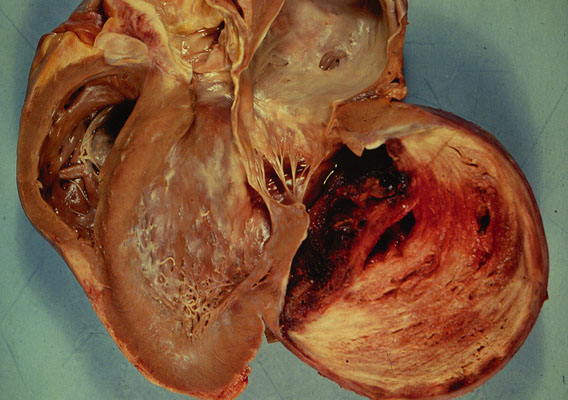

MI, gross

Aneurysm

of the left ventricle. The aneurysm is filled with an organized multilayered

thrombus

. The wall of the aneurysm overlying the thrombus is very thin.